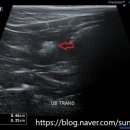

환자들의 후기 등을 미리 살펴보는 것이 도움이 될 수 있습니다. ​ 다음으로, 병원의 시설과 장비 역시 중요한 고려 사항입니다. 최신 진단 장비(예: X-ray, 초음파, 혈액 검사 장비)를 갖추고 있는지, 수술실이나 입원실의 위생 상태는 어떠한지 등을 확인해야 합니다. 특히 응급 상황 발생 시 신속하고 정확한 진단과...

• 선부중앙동물의료센터 | 강아지 요로 결석 재발 재수술 후기

​ ​ ​ 강아지 결석 재발 재수술 후기 강아지 요로결석, 방광결석 재발로 재수술하게 된 후기 남겨봅니다. 반려견 결석은 재발률이 높은 편이라고 해서 꾸준히 관리...이번 수술은 선부중앙동물의료센터에서 진행했어요. ​ ​ ​ ​ 📍선부중앙동물의료센터 정보 주소 : 경기 안산시 단원구 선부광장1로 69 단지내상가동 2층...